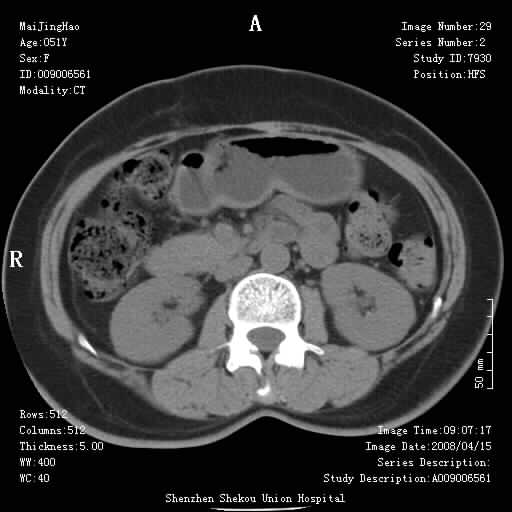

以下是引用余辉在2008-4-26 8:55:00的发言:[br]患者有结石史,此次腹痛4小时,胆总管全程扩张,应有胆总管末端梗阻,此次仍考虑胆结石症,积气不外两种原因,一种是结石下移时肠道内气体逸入,其次为产气菌感染。(倒数第三幅图像于扩张之胆总管末端似可见稍高密度影,考虑为结石影)

以下是引用听蝉观竹在2008-4-26 11:41:00的发言:[br]胆道手术分两种情况:[br]1、如果仅仅做胆囊切除手术,肝内胆管不会积气,只会出现胆总管代偿扩张,因为奥迪氏括约肌依然功能正常胆道与外界并不相通;[br][br]2、胆囊切除+胆总管空肠吻合手术(即roux-y式),则肝内胆管会出现积气,只是因为胆管与小肠相通,气体来源于小肠。这是临床十分常见的手术。[br][br]这个病例应该是胆囊切除+胆总管空肠吻合手术,是正常手术后表现,并不是胆道感染的表现。

以下是引用听蝉观竹在2008-4-27 10:10:00的发言:[br]关于胰头大小问题有几种测量方法和正常值:[br][br]1、直量法:横径<4cm;[br]2、胰头横径与相邻层面椎体横径的比值为二分之一,超过椎体横径就提示胰头增大;[br]3、正常组成年人肠系膜上动、静脉水平夹角正常值范围为4.9°~34.7°大于35°提示胰头增大。[br][br]上述方法只是一种具体的判断,是“量”的评估,更重要的是“质”的评估:一是观察边缘是否光滑,有无局部隆起,有无分叶;二是观察密度(增强,尤其在动脉期和门脉期)是否均匀。[br][br]所以对于胰头是否有异常不仅仅是是目测可以解决问题的,不要轻易就说“胰头增大”。还有一个问题就是测量胰头应该在增强ct上进行,这样可以避免将血管测量进去。[br][br]为什么啰嗦讲怎么多,因为我们实际工作中同样存在影像科医生和临床医生动不动就说胰头增大,说是胰头癌。大家看看是不是这种情况?[br][br] 我个人观点-----本病例的胰头不增大。[br][br][本贴已被 听蝉观竹 于 2008-4-27 10:12:41 修改过]